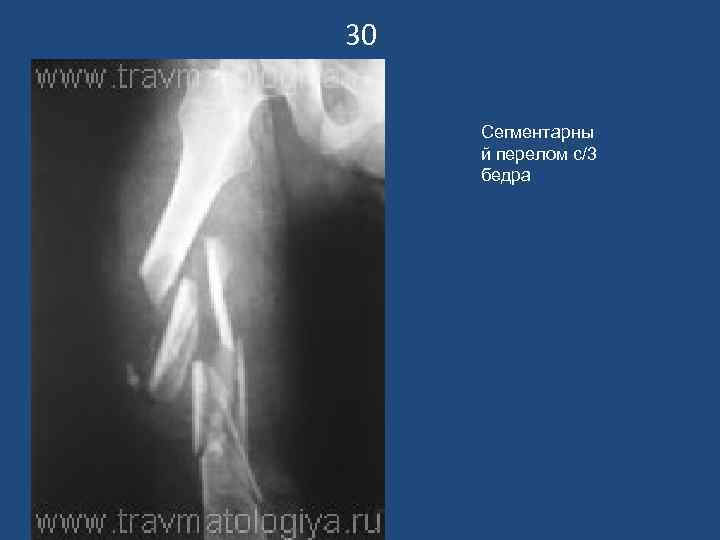

30 Сегментарны й перелом с/3 бедра